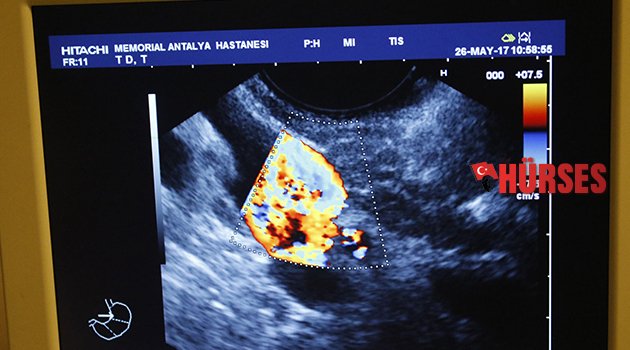

Memorial Antalya Hastanesi Pankreas Hastalıkları Merkezi Bölüm Başkanı Gastroentoroloji Uzmanı Prof. Dr. Yıldıran Songür, mide, bağırsak, pankreas ve karaciğer hastalıklarının yanı sıra endoskopik ve ultrasonografik tanı yöntemleri üzerine çalıştığını kaydetti.

Gastroentorolojinin yemek borusu, mide, bağırsaklar, pankreas, karaciğer ve safra yolları hastalıklarını incelediğini dile getiren Prof. Dr. Songür, "Gastroenterolojik hastalıkların teşhisinde en büyük yardımcımız endoskopik yöntemler. Biz, örneğin kalp ya da böbrek hastalıklarından farklı olarak, sindirim sisteminin, midenin, bağırsakların içine girip, bu organların hastalıklarını çok rahat bir şekilde görüntüleyebiliyoruz. Bu detaylı görüntüleme sonucunda, gerekirse biyopsi alıp patolojik incelemeye gönderebiliyoruz" diye konuştu.